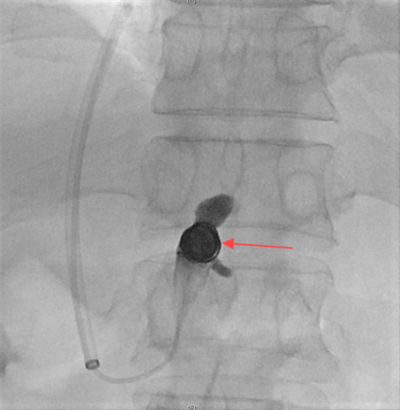

图二:胃底静脉成功栓塞

随后,赵扬程介入手术团队决定为患者施行经颈静脉肝内门体分流术(TIPS),术中经颈静脉入路精准植入8毫米覆膜支架,于肝静脉与门静脉间构建分流通道,同步完成食管胃底曲张静脉栓塞。术后门静脉压力由36厘米水柱降至20厘米水柱,出血立即停止,血红蛋白水平稳定回升。该手术在有效降低血管压力的同时维持肝脏血流灌注,为患者争取到后续治疗的宝贵时间窗。